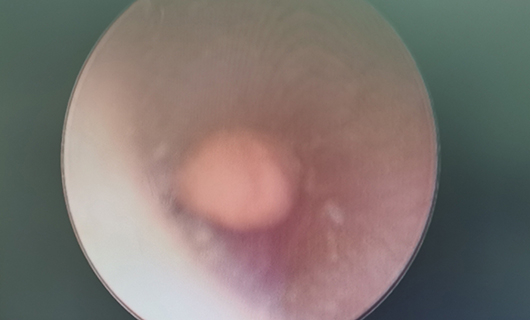

近日,6岁女孩桃桃(化名)因左耳内塞进一块橡皮泥来耳鼻喉科就诊。因为异物位置较深,一碰就疼,桃桃很难配合医生。医生决定做全麻下耳内镜异物取出术,经详细检查、鉴别诊断,启动了日间手术。桃桃就诊当天下午就住院了,手续办齐后,医生为其做了手术。次日早上,桃桃术后一切良好,高高兴兴地出院上学去了。

中国日间手术合作联盟在日间手术的定义中指出,日间手术患者在院时间不超过48小时。耳鼻喉科副主任李莉萍介绍,为了方便患儿,目前耳鼻喉科对耳道异物及鼻腔异物取出术采取日间手术管理,像桃桃这样24小时出院的小患儿,今年到目前为止已有20多例。